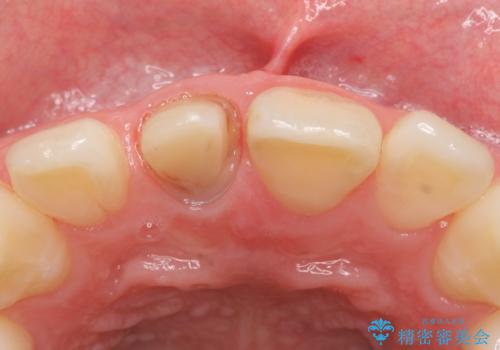

- 右上1番目の前歯の変色が気になるといらっしゃった方の症例です。

再根管治療後、オールセラミッククラウンによる補綴を行いました。

- オールセラミッククラウン…¥100,000、仮歯…¥10,000、ファイバーコア…¥20,000、精密根管治療費別途費用は治療当時の料金となります